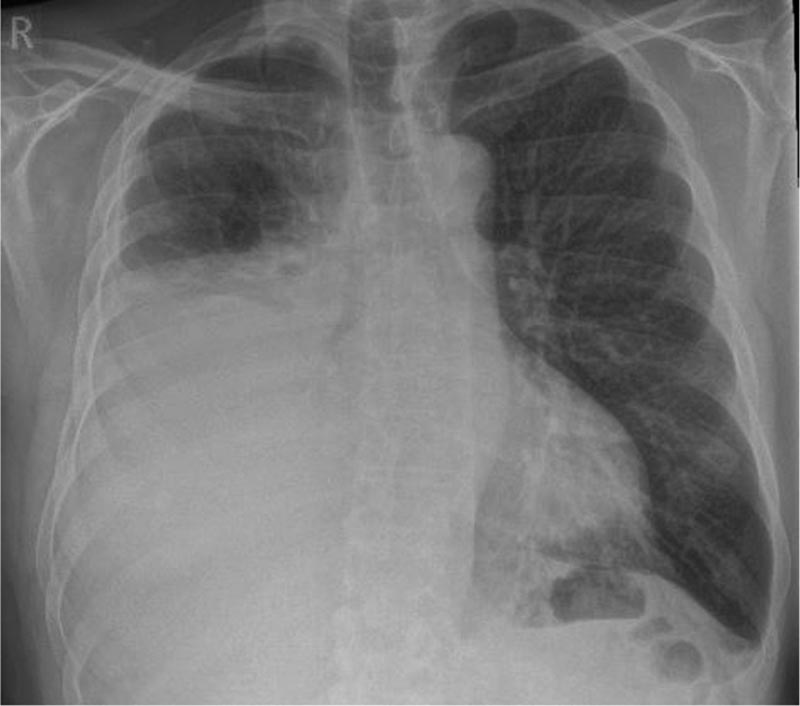

Présentation d’un cas Homme de 67 ans ayant des antécédents de fibrillation auriculaire traitée par edoxaban qui avaient commencé à s’aggraver 4 semaines avant la consultation, avec des difficultés respiratoires. Il est fumeur et consomme 40 paquets par an. Il a déjà été exposé à l’amiante dans le cadre de son travail de constructeur. Le médecin demande une radiographie pulmonaire montrant un épanchement pleural unilatéral (droit) de taille modérée. |

Figure 1 : Radiographie pulmonaire initiale